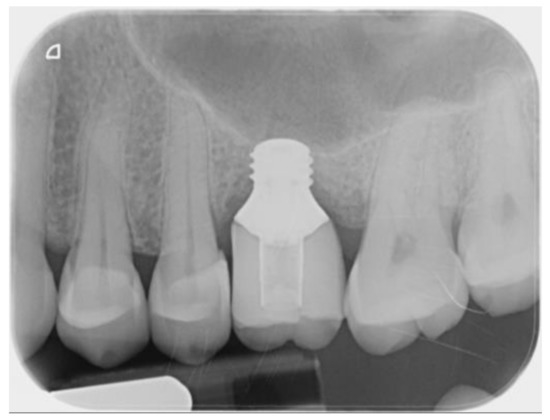

3. Results